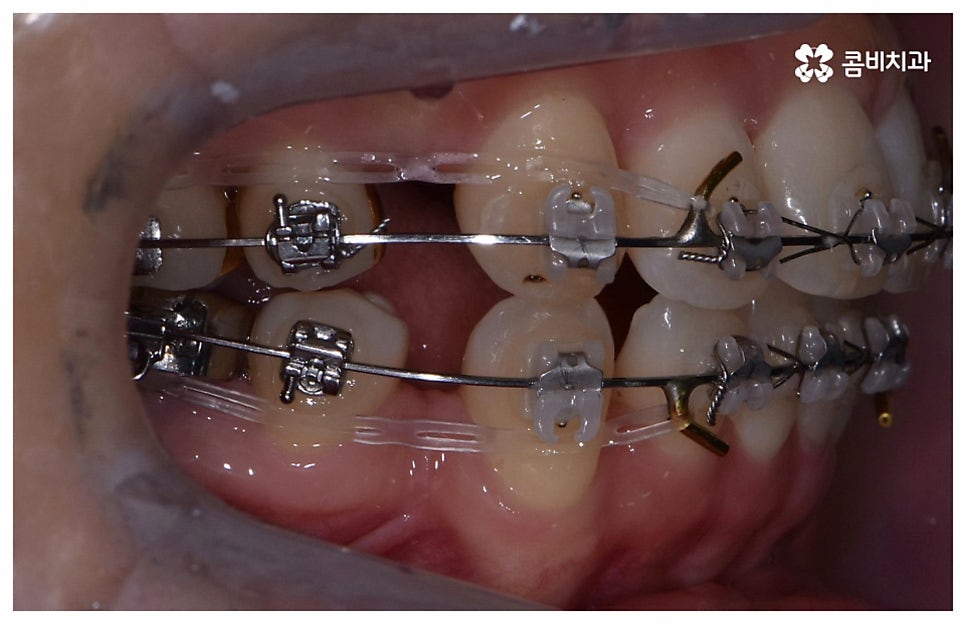

나이가 들어가면서 치아와 주위 조직들이 약해질 수 있고 치주 질환이 발생할 위험도 높아지기 때문에 중년치아교정 치료시 환자분들의 상황에 따른 맞춤 진료를 더욱 세심하게 진행할 필요가 있어요. 교정 방법이나 주의점에 대해서 꼼꼼하게 확인하고 계획을 세워야 할 뿐 아니라 교정 치료 전에 충치나 잇몸병과 같은 구강 질환이 발견되었다면 이를 미리 깨끗하게 치료하고 진행 과정 중간에도 장치에 음식물 찌꺼기가 끼지 않도록 위생 관리를 철저하게 해주며 치료 후 치아와 잇몸이 약해지지 않도록 환자분들 각각의 치아 이동 속도에 따라 무리하지 않는 것이 중요한 포인트라고 할 수 있습니다.

검진 후 부분 교정이 가능하지 않은 케이스라고 해도 요즘은 심미적인 교정 장치가 많이 나와 있으며 장치 자체로 인해 결과에 미치는 영향이 크지 않기 때문에 자신의 상황에 맞는 장치를 직접 선택할 수 있으니 의료진과 충분히 상담을 해 보시면 도움 받아 보실 수 있을 거예요. 특히 치아 색상의 브라켓을 이용한 세라믹 장치들이 심미성이 뛰어난데, 그 중에서도 자가결찰방식을 이용한 클리피씨 교정 장치를 이용하면 눈에 크게 띄지 않을 뿐 아니라 보다 적은 힘으로 부드럽고 지속적인 치아 이동을 가능하게 하기 때문에 통증도 줄이고 전체 교정 기간 역시 단축시킬 수 있다는 장점이 있으니 이에 대해서도 자세하게 알아보시길 바라고 있습니다.

위 사진은 환자분의 동의를 받아 이해를 돕기 위한

사진이며, 실제 치료 결과는 다를 수 있습니다.